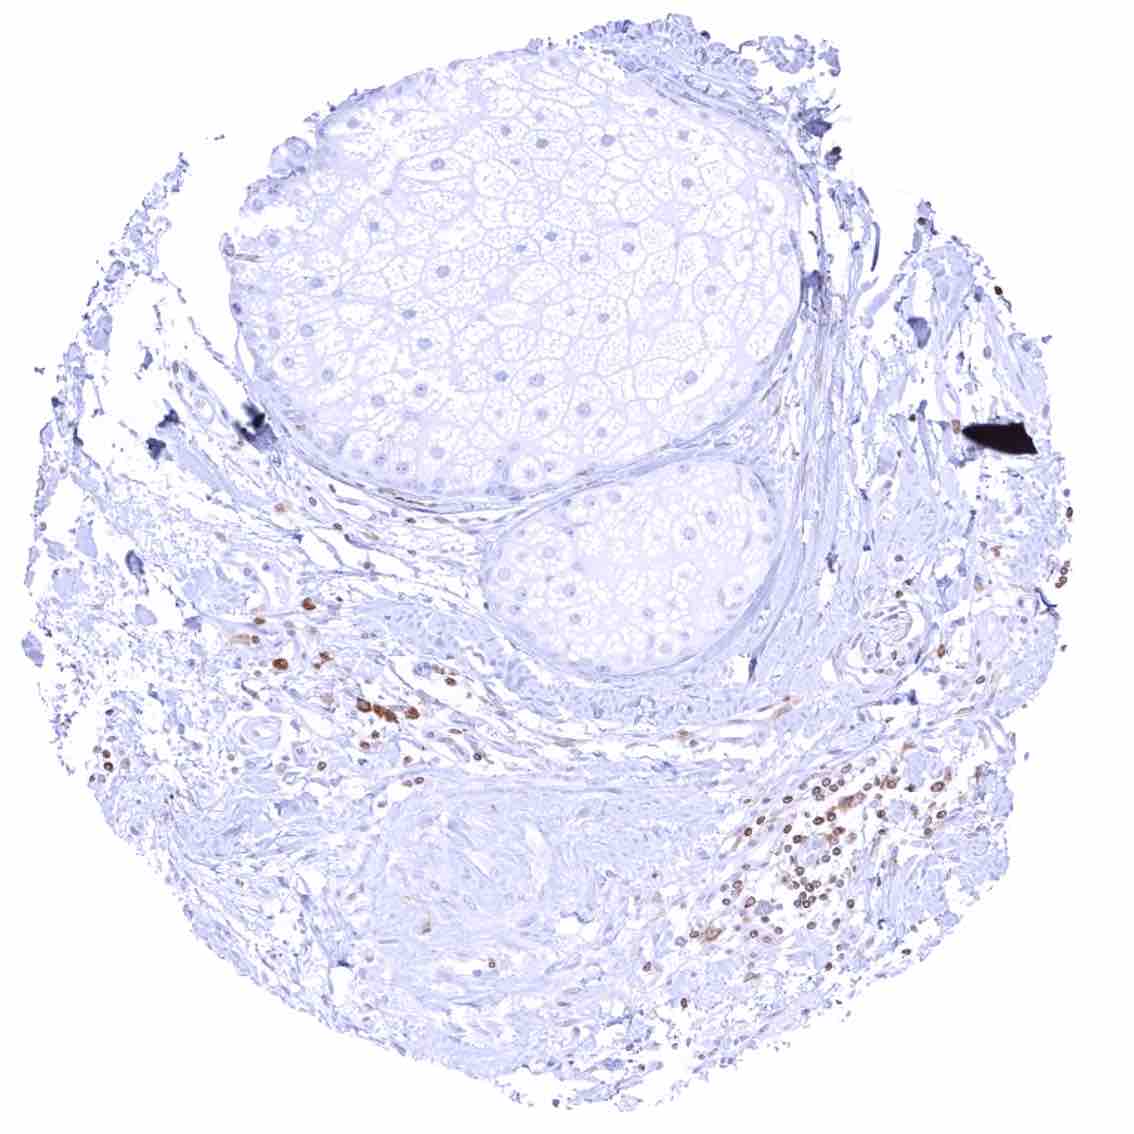

Ovary, corpus luteum

Ovary, stroma – Strong cytoplasmic bcl-2 staining of stroma cells.